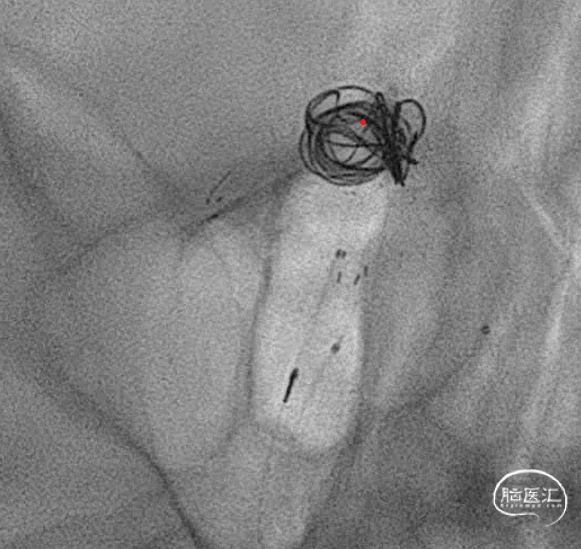

先填一个适当大小的圈,刚开始微导管头位置感觉差一些,借着弹簧圈比较软的优势,适当跟了一点微导管,感觉这个位置应该可以了,首先因为是大动脉瘤,通过简单的填塞很难把动脉瘤栓塞致密,因此一般选择分区填塞,因此计划是先把8,9点位置填的差不多后再回撤微导管,在回撤轨迹将弹簧圈依次填塞使其致密,但是凡事都是:身后有余忘缩手,眼前无路想回头。所以一切计划都存在变数。

第一个圈盘的还可以,直接支架辅助,一切都很顺利。微导管头的位置按原计划可行。

第一个圈填完,成型不错,弹簧圈微导管由于圈的张力作用,稍好低了一下头(红色标记),不过还好。